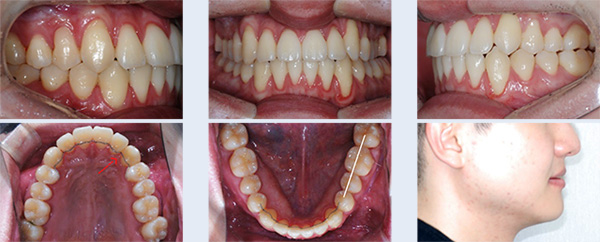

앞니 치열 불규칙하고 어금니가 잘 맞물리지 않아 소리가 나는 증상으로 내원한 22세 대학생입니다. 좌측 위 덧니가 관찰되었고 아래 어금니 배열이 바르지 않아 위 어금니와 정상적인 교합 관계를 보이지 않는 상태였습니다. 이를 빼지 않고 공간을 확보하기 위해 다음의 치료를 진행하였습니다.

① 위 치열을 측방으로 넓히기 위해 TPA(transpalatal arch, 횡구개호선) 사용

② 교정용 미니스크류(miniscrew)를 이용하여 사랑니가 있던 공간으로 위 어금니 후방 이동

③ 아래 치열 중간에 공간을 형성하기 위해 치간 삭제(interproximal stripping)

앞니 치열이 고르게 개선 되었으며 어금니가 자연스럽게 맞물리는 정상교합이 되었습니다. 자연치아를 빼지 않고 약간의 치간 삭제를 통해 교정 치료가 완료되어 환자 분의 만족도가 높은 케이스였습니다.